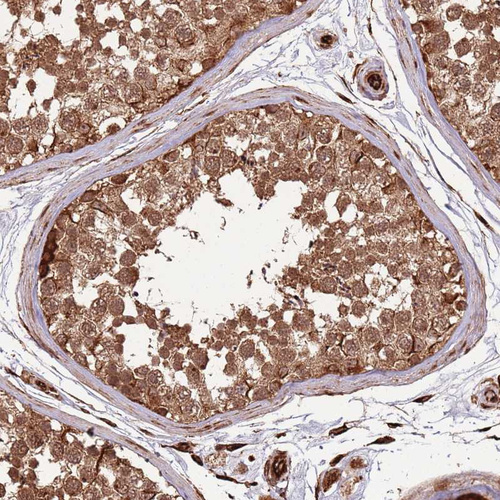

Immunohistochemical staining of human testis shows strong cytoplasmic positivity in cells in seminiferous ducts.